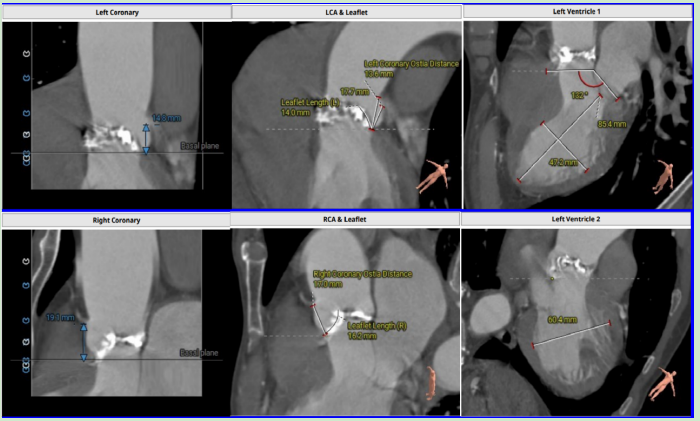

該患者為74歲的老年男性,因長(zhǎng)期反復(fù)胸悶、呼吸困難近兩年多次住院治療,經(jīng)過(guò)系統(tǒng)的檢查,該患者被診斷為主動(dòng)脈瓣重度狹窄伴中重度返流,室間隔增厚,二、三尖瓣輕中度反流。

主動(dòng)脈根部及外周入路血管

主動(dòng)脈根部

冠脈阻擋風(fēng)險(xiǎn)及左室大小評(píng)估

針對(duì)這種病傳統(tǒng)的治療方法是外科開胸行主動(dòng)脈瓣和二尖瓣置換術(shù),但該患者由于高齡、重度消瘦,身體體質(zhì)衰弱,且合并房顫及多系統(tǒng)疾病,評(píng)估不適合接受常規(guī)外科手術(shù)置換瓣膜,無(wú)法進(jìn)行外科手術(shù)。